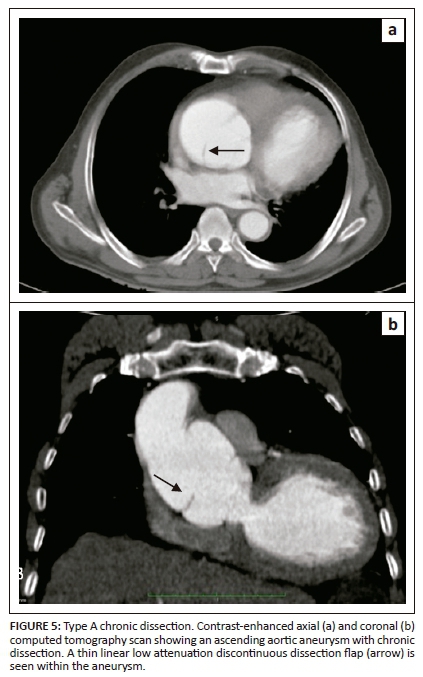

On unenhanced CT, intraluminal displacement of intimal calcifications can occasionally be seen, suggesting AD (Figure 1). A linear hypodense internally displaced structure representing the intimo-medial flap, separating the true and false lumens, is the most important CT finding seen in approximately 70% of cases (Figures 2, 5 and 8c).7 In the present era of endovascular management, differentiation of the true and false lumen is important in planning the management. The true lumen directly communicates with the aorta, and intimal calcifications, if present, surround it (Figure 3a). The calibre of the true lumen is smaller as compared to false lumen, which wedges around it owing to permanent systolic pressure. Fine linear scattered hypodense areas within the false lumen are termed the Cobweb sign (Figure 3a). It is specific for the false lumen and represents collagenous residual media fibres.8 The beak sign is another useful sign for the false lumen which represents a wedge of haematoma at the distal end of the false lumen on cross-sectional imaging (Figure 3b). It forms an acute angle between the dissection flap and vessel wall and represents the site of propagation.9 The false lumen shows less contrast enhancement compared to the true lumen in the early arterial phase and may appear hyperdense to the true lumen in the venous phase owing to contrast pooling (Figure 4).

Aortic dissection with a thrombosed false lumen could mimic an aortic aneurysm with intraluminal thrombus. Intimal calcifications are useful in differentiating between them, as they are located in the centre in AD and at periphery in aortic aneurysm with thrombus. The dissection flap in AD has a smooth contour, whereas mural thrombus usually has an irregular internal surface.